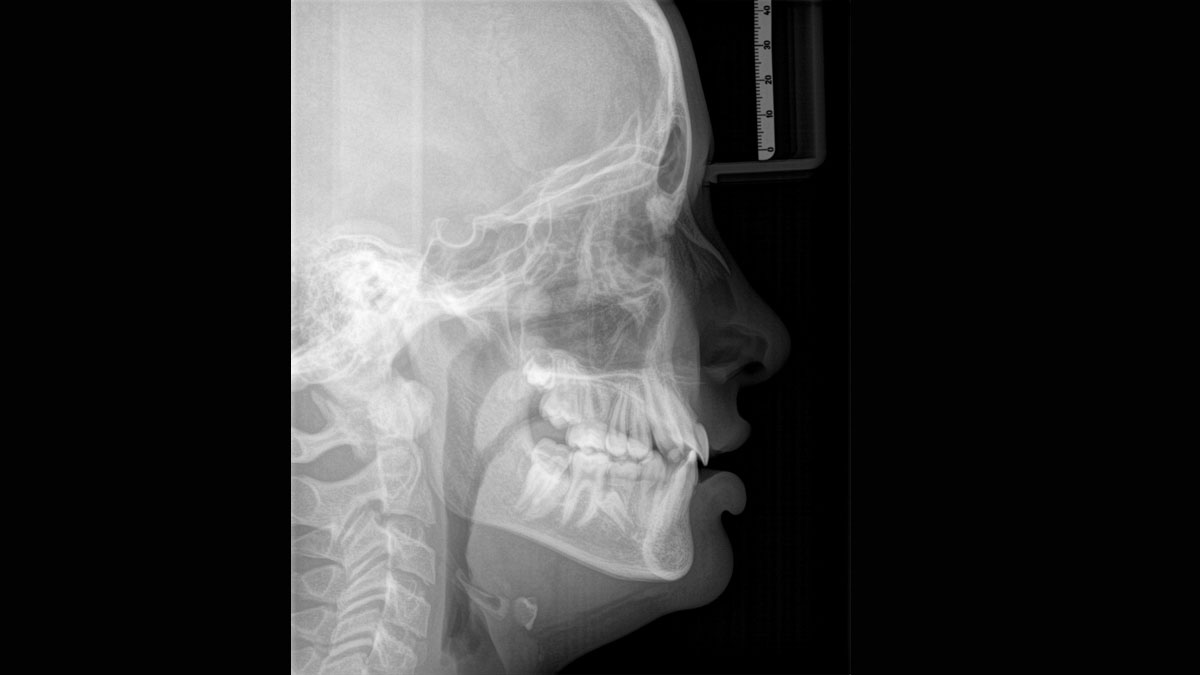

Ramię cefalometryczne można dodać po prawej lub lewej stronie urządzenia i zamówić w momencie zakupu lub dodać w dowolnym momencie